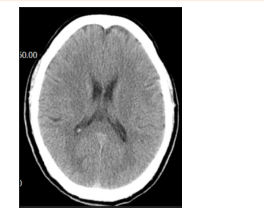

急診心電圖:未見明顯異常。頭顱CT:如圖。

(3)頭顱CT未見明顯異常,可排除腦出血。(0.5分)